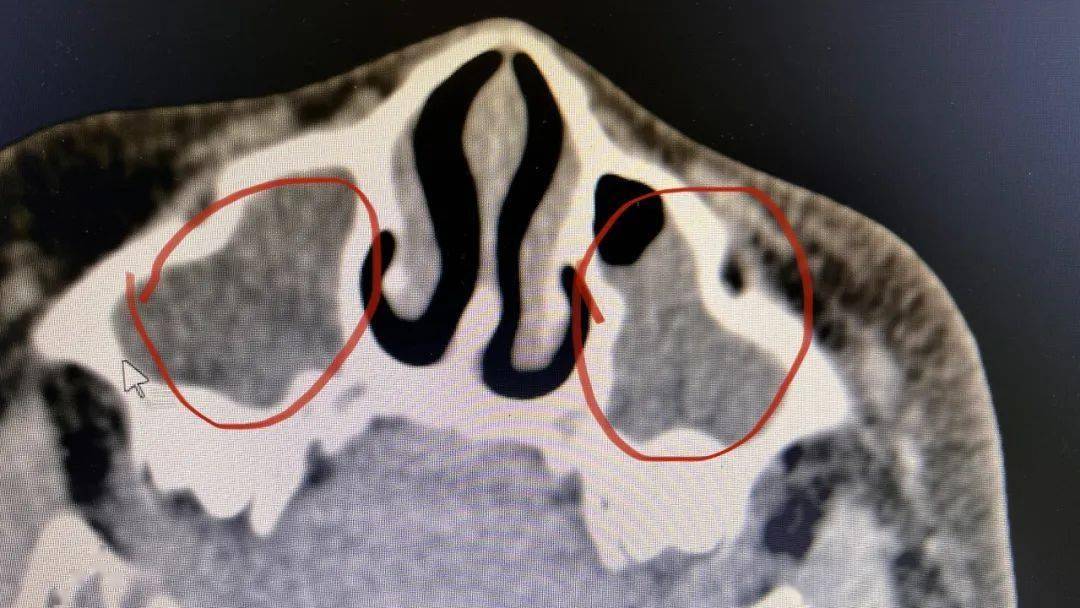

5mmct和mri也可以用于腺样体肥大的评估,ct和mri能够多方位显示腺样体

正常情况下,咽部穹窿光滑平整,如果腺样体增生,肥大就会突出于气道